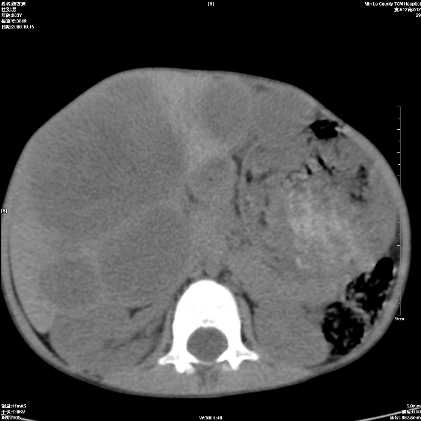

标题: PED1609:男性,3岁。彩超示肝Ca. [打印本页]

标题: PED1609:男性,3岁。彩超示肝Ca.

考虑后纵隔恶性畸胎瘤伴肝内多发转移可能性大,右侧肾上腺转移不除外.

考虑后纵隔恶性畸胎瘤伴肝内多发转移可能性大,右侧肾上腺转移不除外

考虑后纵隔恶性畸胎瘤伴肝内多发转移可能性大,右侧肾上腺转移.

后纵隔恶性畸胎瘤,肝内多发转移可能性大,